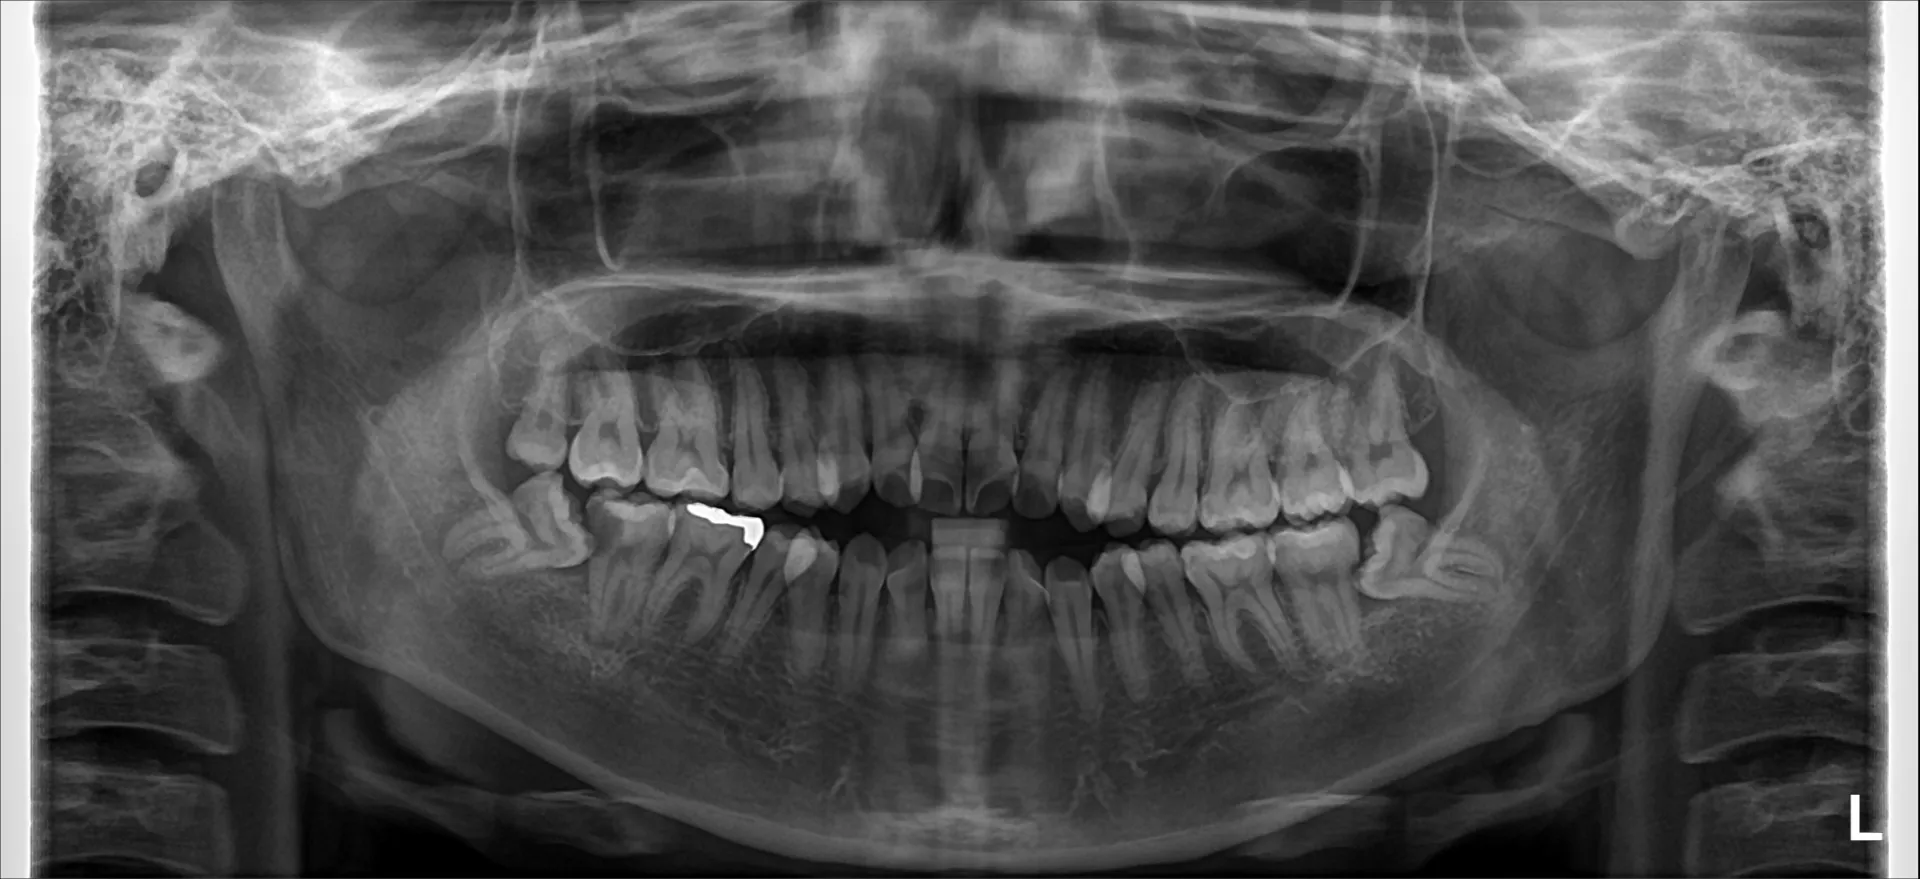

まず親知らずのレントゲン写真を2つお見せします。

どちらも横向きに生えた親知らずですが、抜歯の難易度は大きく異なります。

難易度ではレントゲン写真1>レントゲン写真2となります。

・横向きであることは同じですが、角度は大きく違います。

写真1は下に向かっている。写真2は上に向かっている。

抜歯は口腔内から治療を行うために、上に向いている方が器具が届きやすく、目で見える範囲で治療を行うことができます。

・骨に埋まっている範囲は写真1>写真2。

骨に埋まっている範囲が大きければ大きいほど骨を切削して掘り出す必要が出てきます。

周りの骨を削合すれは当然創傷は大きくなり、腫れや出血、痛みなどの症状も出やすくなります。

・下顎管(神経や血管のある管)との距離や歯の接している範囲

下顎管の損傷は神経麻痺のリスクや大量出血のリスクが大きくともなってきます。

近ければ近いほど、範囲が多ければ多いほど慎重に治療を行う必要があるために抜歯時間も長くなる傾向にあります。

・歯根の開き方

歯根は写真1は単根と言って1つにまとまっています。しかし写真2では2根にはっきりと分かれていてカニの爪のように彎曲もしています。

この場合は写真2の方が難易度は上がってきます。